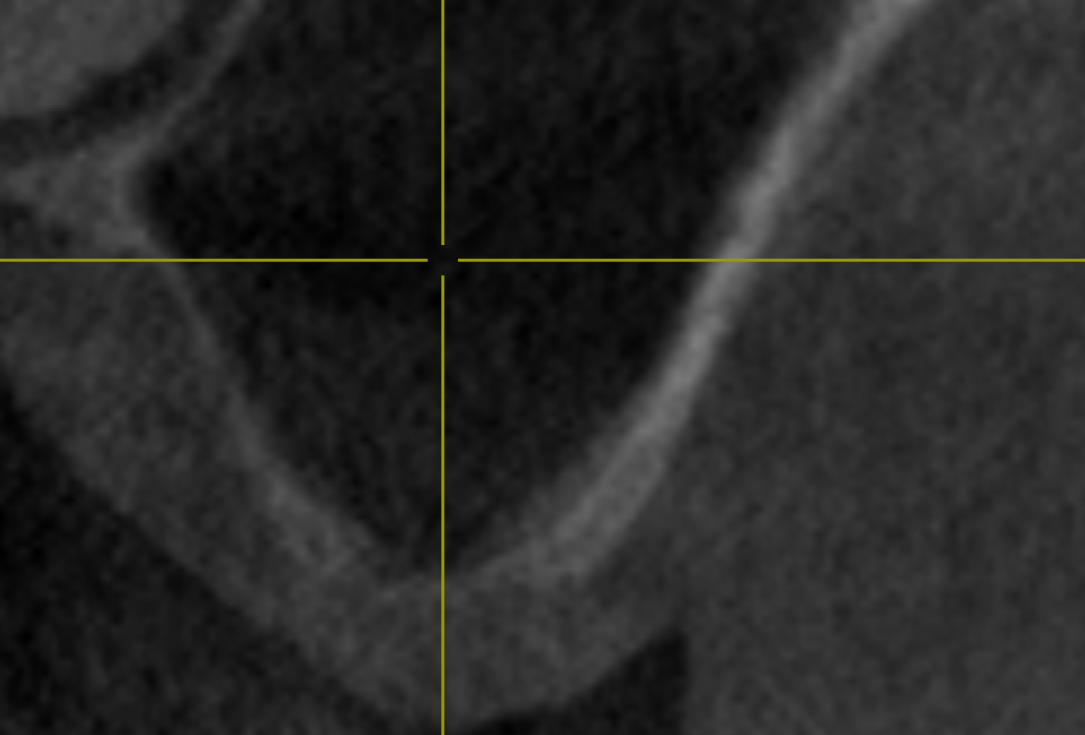

02/14 - Transversal section to determine depths of the sinus floor

Two-stage sinus lift with maxresorb® & collprotect® - Dr. S. Kistler